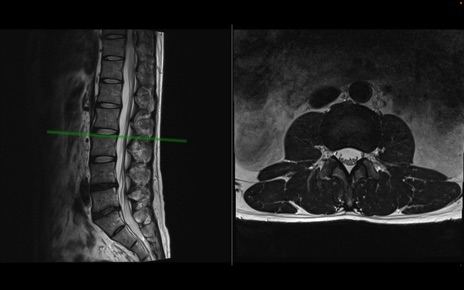

【整形】TIPS症例1 腰椎MRI 横断像と矢状断像

【症例】40歳代男性

【主訴】左臀部〜大腿後面痛み

【現病歴】2週間前から腰痛あり。2日前に夜中にくしゃみをした際に激痛が出現。疼痛強いため来院。

【身体所見】左臀部〜大腿後面、下腿後面のしびれ。SLR -/+ 30度、うつ伏せ困難、筋力低下なし。

異常所見と診断は?